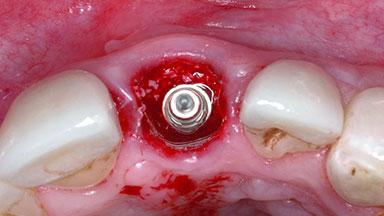

Placement Protocol Immediate implant placement

Socket Morphology Single-root socket

Socket Integrity Damage to one or more bone walls

Bone Volume Damage to one or more socket walls